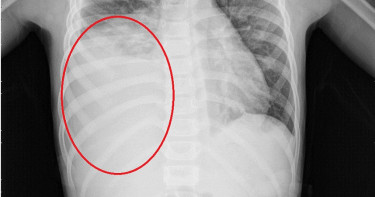

5歲女童肺積水 量多猶如一瓶可樂

發燒、咳嗽是孩童生病時最常見的症狀,5歲陳小妹妹因反覆高燒達40度及劇烈咳嗽至他院就醫,因狀況未改善,遂改至醫院就診,經胸部X光發現有大量肺積水約500cc(相當於1瓶可樂),經插胸管引流胸水,血液及胸水檢驗結果是黴漿菌感染引起大量肺積水,即使入院便使用正確抗生素治療,病童仍住院3個星期後才退燒。國泰綜合醫院小兒科沈仲敏主任指出,黴漿菌不是黴菌,是一種沒有細胞壁的微生物。在台灣,一年四季都可見到黴漿菌感染病例,但好發於春夏交替及秋天時節,一般侵犯的年紀多為3歲以上孩童及年輕成人,2歲以下的嬰幼兒病例數較少,主要感染的年齡層在5〜15歲之間,尤其在團體中更容易感染。黴漿菌抗體沒有終生保護效果,所以會再次感染,而黴漿菌的傳染途徑是經由飛沫傳染,需要人對人的傳染,它的潛伏期可長達2~3週。因此,臨床上,常見全家或學校同一班級內輪流感染達數月之久。黴漿菌感染不一定會先以發高燒表現,有時是久咳,起初大多沒什麼痰,後來才出現白色黏痰或帶有血絲的膿痰,可以持續到3〜4週,引起肺積水並不常見,其他同時會出現的症狀還有寒顫、咽喉炎、嘔吐、腹痛、皮膚疹等。值得注意的是兒童比成人更容易會發高燒。由於黴漿菌肺炎的病人其排菌時間可長達3〜4個月之久,經常會造成學校、家庭及社區內的群體感染,以上述案例來說,如此嚴重的肺積水是不常見的,然因黴漿菌目前並沒有疫苗,感染之後也沒有終生免疫,因而提醒各位家長,如果發現孩子出現咳嗽、發燒久久不癒,應盡早就醫檢查,以免延誤病情。尤其在秋天流行季節,建議應常洗手、戴口罩,盡可能減少出入人潮密集的地方,是預防黴漿菌感染的有效方法。